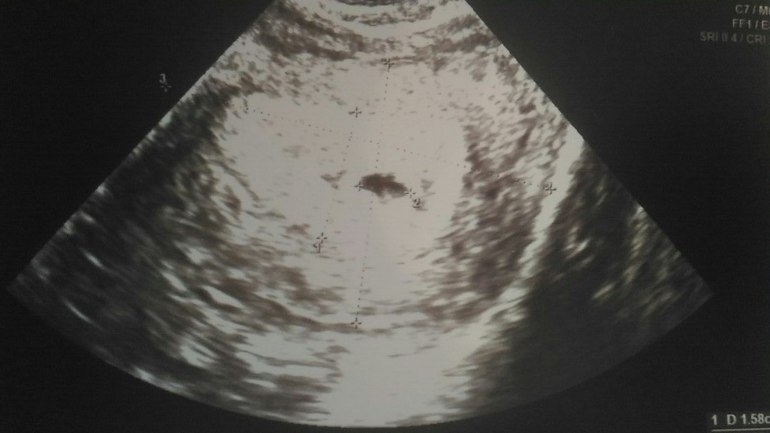

В общем сказали все нормально, эндик хороший, ЖТ соответствует, и т.д. Но ПЯ деформировано. Врач вроде норм, сказала, что скорее всего просто из-за срока и все выровняется. Предложила утрожестан ставить до следующего контроля через 10-14 дней, но это на наш выбор и не обязательно. Как вы считаете? С прогестероном вроде проблем не было никогда, да и про деформацию сколько не читала, вроде как на этом сроке не критично.

Снимки:

Трансвагинально

Да вот оно с одной стороны такое, а с другой со вмятинкой как бы, как у луны неполной) Спасибо за мнение)